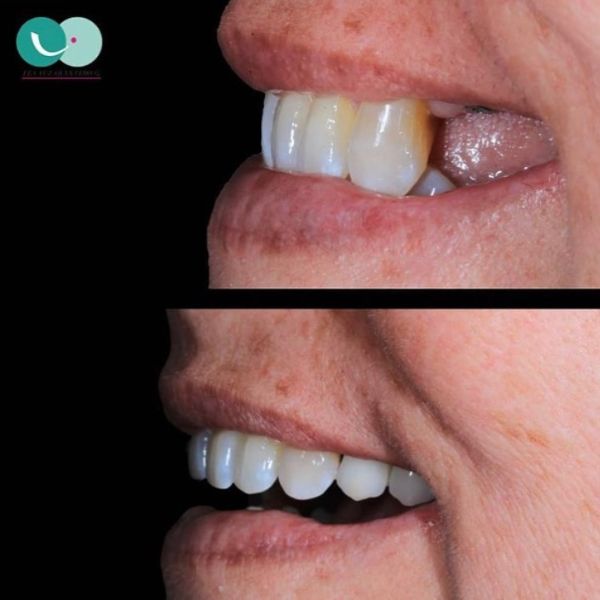

Before and After Gallery

Estoy completamente felizzzz , me realizaron implantes con coronas de Zirconio y láminas en cerámica en los dientes de adelante superiores y tuvo el mejor cuidado para complementar el color de mi dentadura de manera muy perfecta , la felicidad es toda , demasiado profesional y ética , estoy completamente feliz , Me hizo otros tratamientos donde implicaba mucho tiempo y la constancia y dedicación me sorprendió y lo logró en el menor tiempo posible , es sorprendente su empatía con el paciente, muchas gracias Doctora Eva